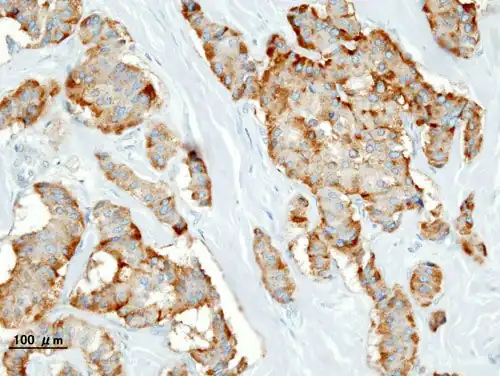

| Pathology of pancreatic endocrine tumour (insulinoma). | |

Chromogranin A

Insulin immunostain